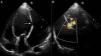

Case reportA 60-year-old male, a chronic smoker for more than 20 years and hypertensive for more than five years, presented to our institute with orthopnea for two weeks, despite optimized treatment for congestive heart failure on an outpatient basis. He had suffered an acute inferior wall MI five months previously, when coronary angiography revealed significant stenosis of the left circumflex artery, and underwent successful angioplasty and stenting. His electrocardiogram showed sinus tachycardia and non-specific persistent ST-T wave changes. Two-dimensional echocardiography and color Doppler (iE33 xMATRIX, Philips Healthcare, Andover, MA, USA) were remarkable, in addition to severe LV dysfunction, for the presence a large pseudoaneurysm lateral to the LV free wall communicating with the ventricular cavity, with the neck measuring 14 mm (Figure 1). The large aperture communicating between the LV and pseudoaneurysm was almost circular, with muscular rims, and the chordal attachment was 12 mm from the nearest margin. In view of the risk of surgery associated with severe LV dysfunction and heart failure, percutaneous closure of the defect was selected by a combined decision of interventionists and surgeons. After written informed consent was obtained in accordance with institutional protocols, retrograde transcatheter closure of the LV pseudoaneurysm was planned using an Amplatzer septal occluder (AGA Medical Corp, Plymouth, MN, USA) under transthoracic echocardiography guidance.